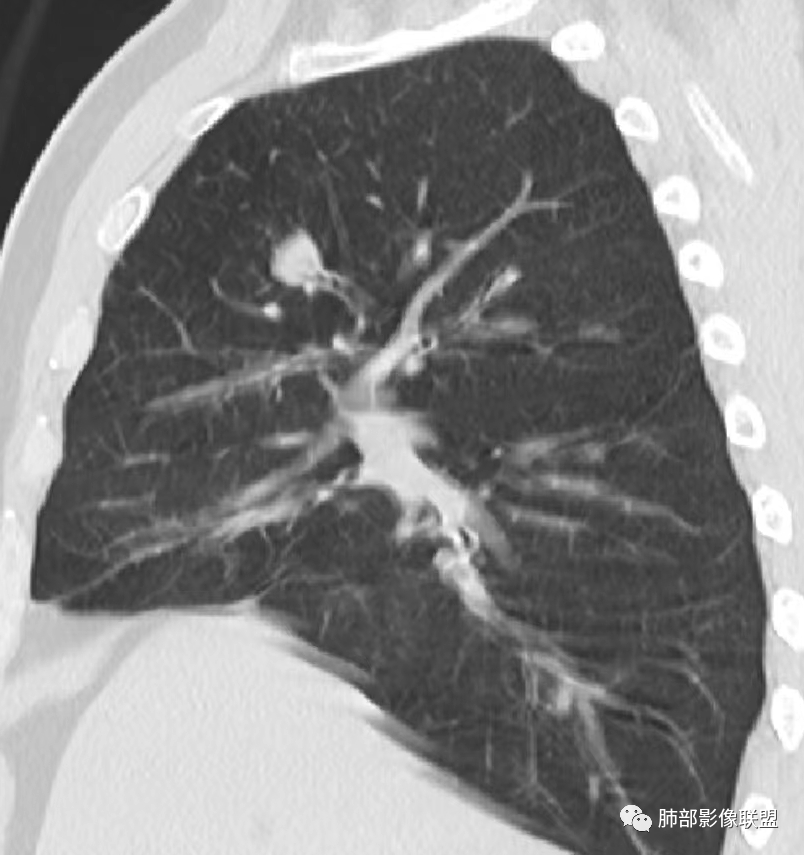

老年男性患者,长期吸烟史,没有呼吸系统临床表现。胸部CT示右肺上叶实性密度结节影,密度均匀,未见空洞及钙化,边缘较光整,未见分叶及毛刺。血管影旁现侧出,支气管进入并截断,不均匀强化。

影像上结节影或块影一旦与支气管密切相关(如截断),不支持硬化性肺细胞瘤、错构瘤、孤立性纤维瘤等良性病灶。如此清晰的边缘也不符合一般意义上的炎性渗出。

恶性病灶需要排除的有神经内分泌癌(大细胞癌、小细胞癌、类癌)、鳞癌、淋巴瘤样上皮癌、淋巴瘤等等。

——本例鳞癌病理意见可以符合,只是太光整、太干净,且病灶不大,未能显示出坏死等特征,我们从影像上难以得出倾向性意见。